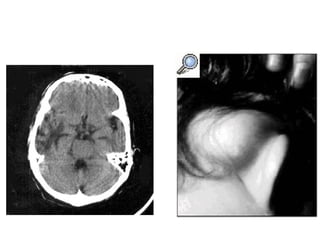

Mastoiditis.

Existe un absceso subperióstico, lateral, que puede afectar los espacios cervicales

(mastoiditis de Bezold).

Se encuentra como consecuencia de infección latente, puede aparecer pasadas dos

semanas del comienzo del cuadro de sobre infección de OMC.

•Otorrea

•Fiebre

•Dolor

•En 48% hay absceso retroauricular

•Son mas frecuentes en los niños que

en adultos.

•Necrosis parcial del conducto auditivo

externo.

•Dolor latente y una importante

exacerbación del mismo al presionar la

punta de la mastoides (signo de Caliceti)

•O el trago (signo de Vacher).

•Leucocitosis

Los exámenes radiológicos, será radiología simple (Shuller l) o TC, que permiten

apreciar la destrucción ósea.